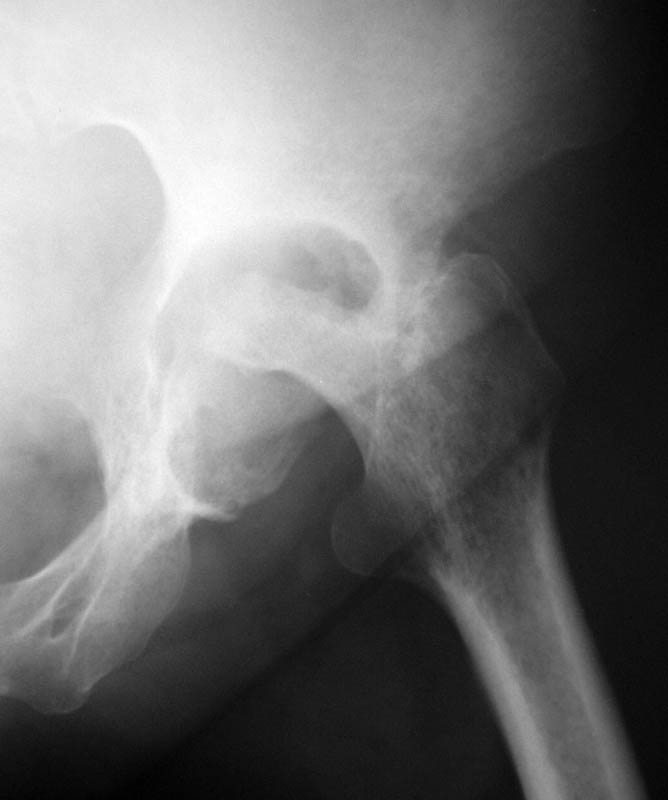

Женщина, 45 лет. В марте перенесла левосторонний коксит неизвестной этиологии. Специфику и онкологию исключили.

Интраартикулярных инъекций не было. Сейчас процесс клинически и рентгенологически - стабилизировался. Состояние вполне удовлетворительное.Предполагается тотальное эндопротезирование с пластикой полости аутокостью. Возможна ли бесцементная <чашка>? Заранее благодарю! С уважением,А.В.Владзимирский

Пртезирование через пол года после коксита закончившегося лизисом сустава, который на снимках выглядит как гнойный? Что значит неизвестной этиологии?

Уважаемый коллега! Последняя версия - мы пролистали ренгенологическую книженцию-так картинка вполне подходит под сустав Шарко (neuropatic joint ). В тазобедренном суставе патология редкая (но меткая). Ищите причину - варианты - нейросифилис, сирингомиелия, опухи спинного мозга (и выше тоже) компрессия спинного

мозга извне, рассеяный склероз, алкоголизм. А так-же : склеродерма ,Рейно,ревматоидный артрит, амилоидная инфильтрация нервов,и это не считая всяких менингеомиелоцеле,asymbolia,Riley-Day syndrom,и все возможные другие нейропатии. На данном этапе не спешите оперировать(протезирование протиопоказано при нейропатических суставах),проконсультируйтесь с классным невропатологом,сделайте МЯР головного озга и